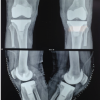

At 13 weeks, the patient presented with acute onset of pain and swelling over the posterior aspect of left knee, which progressed to involve the calf. On examination, there was no anterior knee tenderness, but tenderness was present along the posterior aspect of thigh extending to the calf. There was a cystic swelling at the popliteal fossa which was limiting knee flexion, and pain was aggravated with exercises, especially with dorsiflexion of the foot. Homan’s sign was also found to be positive. The initial suspicion was DVT and a diagnostic workup including radiographs of bilateral knee joints, color venous doppler to rule out DVT, and ultrasound (USG) of the popliteal fossa to look for any collection were done. Radiographs showed a well-fixed implant and did not show any signs of infection or loosening (Fig. 2A-D). Doppler showed a 2.7 cm ×1.8 cm ×6.0 cm hypoechoic collection in the intermuscular plane at the upper part of popliteal fossa, along with internal septations with differential diagnosis of a resolving hematoma or a ruptured popliteal cyst (Fig. 2E, F). There was no evidence of DVT. A 1.5 Tesla contrast-enhanced magnetic resonance imaging (MRI), confirmed the findings of the Doppler study; it showed the fluid from the ruptured cyst extending distally along the intermuscular gastrocnemius plane. The blood workup including total leukocytes count (7600), erythrocyte sedimentation rate (ESR- 15 mm at 1st h), and quantitative C-reactive protein (CRP-6 mg/l) were all within normal limits. The D dimer level was also normal.

A 51-year-old female presented to our outpatient department with bilateral knee pain and difficulty in ambulation without aid. On examination, she had bilateral medial joint line tender-ness and an antalgic gait with bilateral varus thrust. Plain radiographs confirmed bilateral Grade 4 osteoarthritis (Fig. 3A-D). Bilateral TKA was done on July 27, 2015, using CS Genesis II from Smith and Nephew. The patient had an uneventful intraoperative and post-operative course with physiotherapy and aided ambulation initiated on the 2nd day after the surgery. On follow-up, the patient was pain free, was doing active physiotherapy exercises with knee flexion range of 0–1100 bilaterally, and was walking without support. Three years later, she had a fall in her bathroom and presented with pain and swelling in the left knee. She complained of the presence of a swelling in the left popliteal area for 1 year, for which she was consulting a local medical practitioner; after the fall, she developed pain in the knee for which she was referred to the primary operating surgeon. On examination, a tender swelling was palpable in the popliteal fossa, extending up to the mid-calf (Fig. 4A, B). Homan’s sign was negative and the knee flexion was restricted due to pain in the knee. All blood tests to rule out infection were within the normal range. The ESR was 12 mm at 1st hour and the quantitative CRP was 6 mg/l. The total white blood cells count was 9500 and the D- dimer levels were normal. Radiographs showed no evidence of osteolysis, fracture, or implant loosening (Fig. 5A-D). Color Doppler for DVT was negative. The USG of the cyst showed hypoechoic echoes in a Baker’s cyst-like collection (Fig. 6). Aspiration under all aseptic conditions was done, and cytological findings were suggestive of hemorrhagic nature of the aspirate, without any evidence of polyethylene debris. The cultures were sterile. The patient was advised rest, graduated physiotherapy, and minimal walking with stick. She became asymptomatic over the next 4 weeks; but a mild swelling persisted for 3 months. The patient has been asymptomatic with no complaints, and even at the last follow-up at 4-year post-TKR, there was no evidence of any implant-related issues.